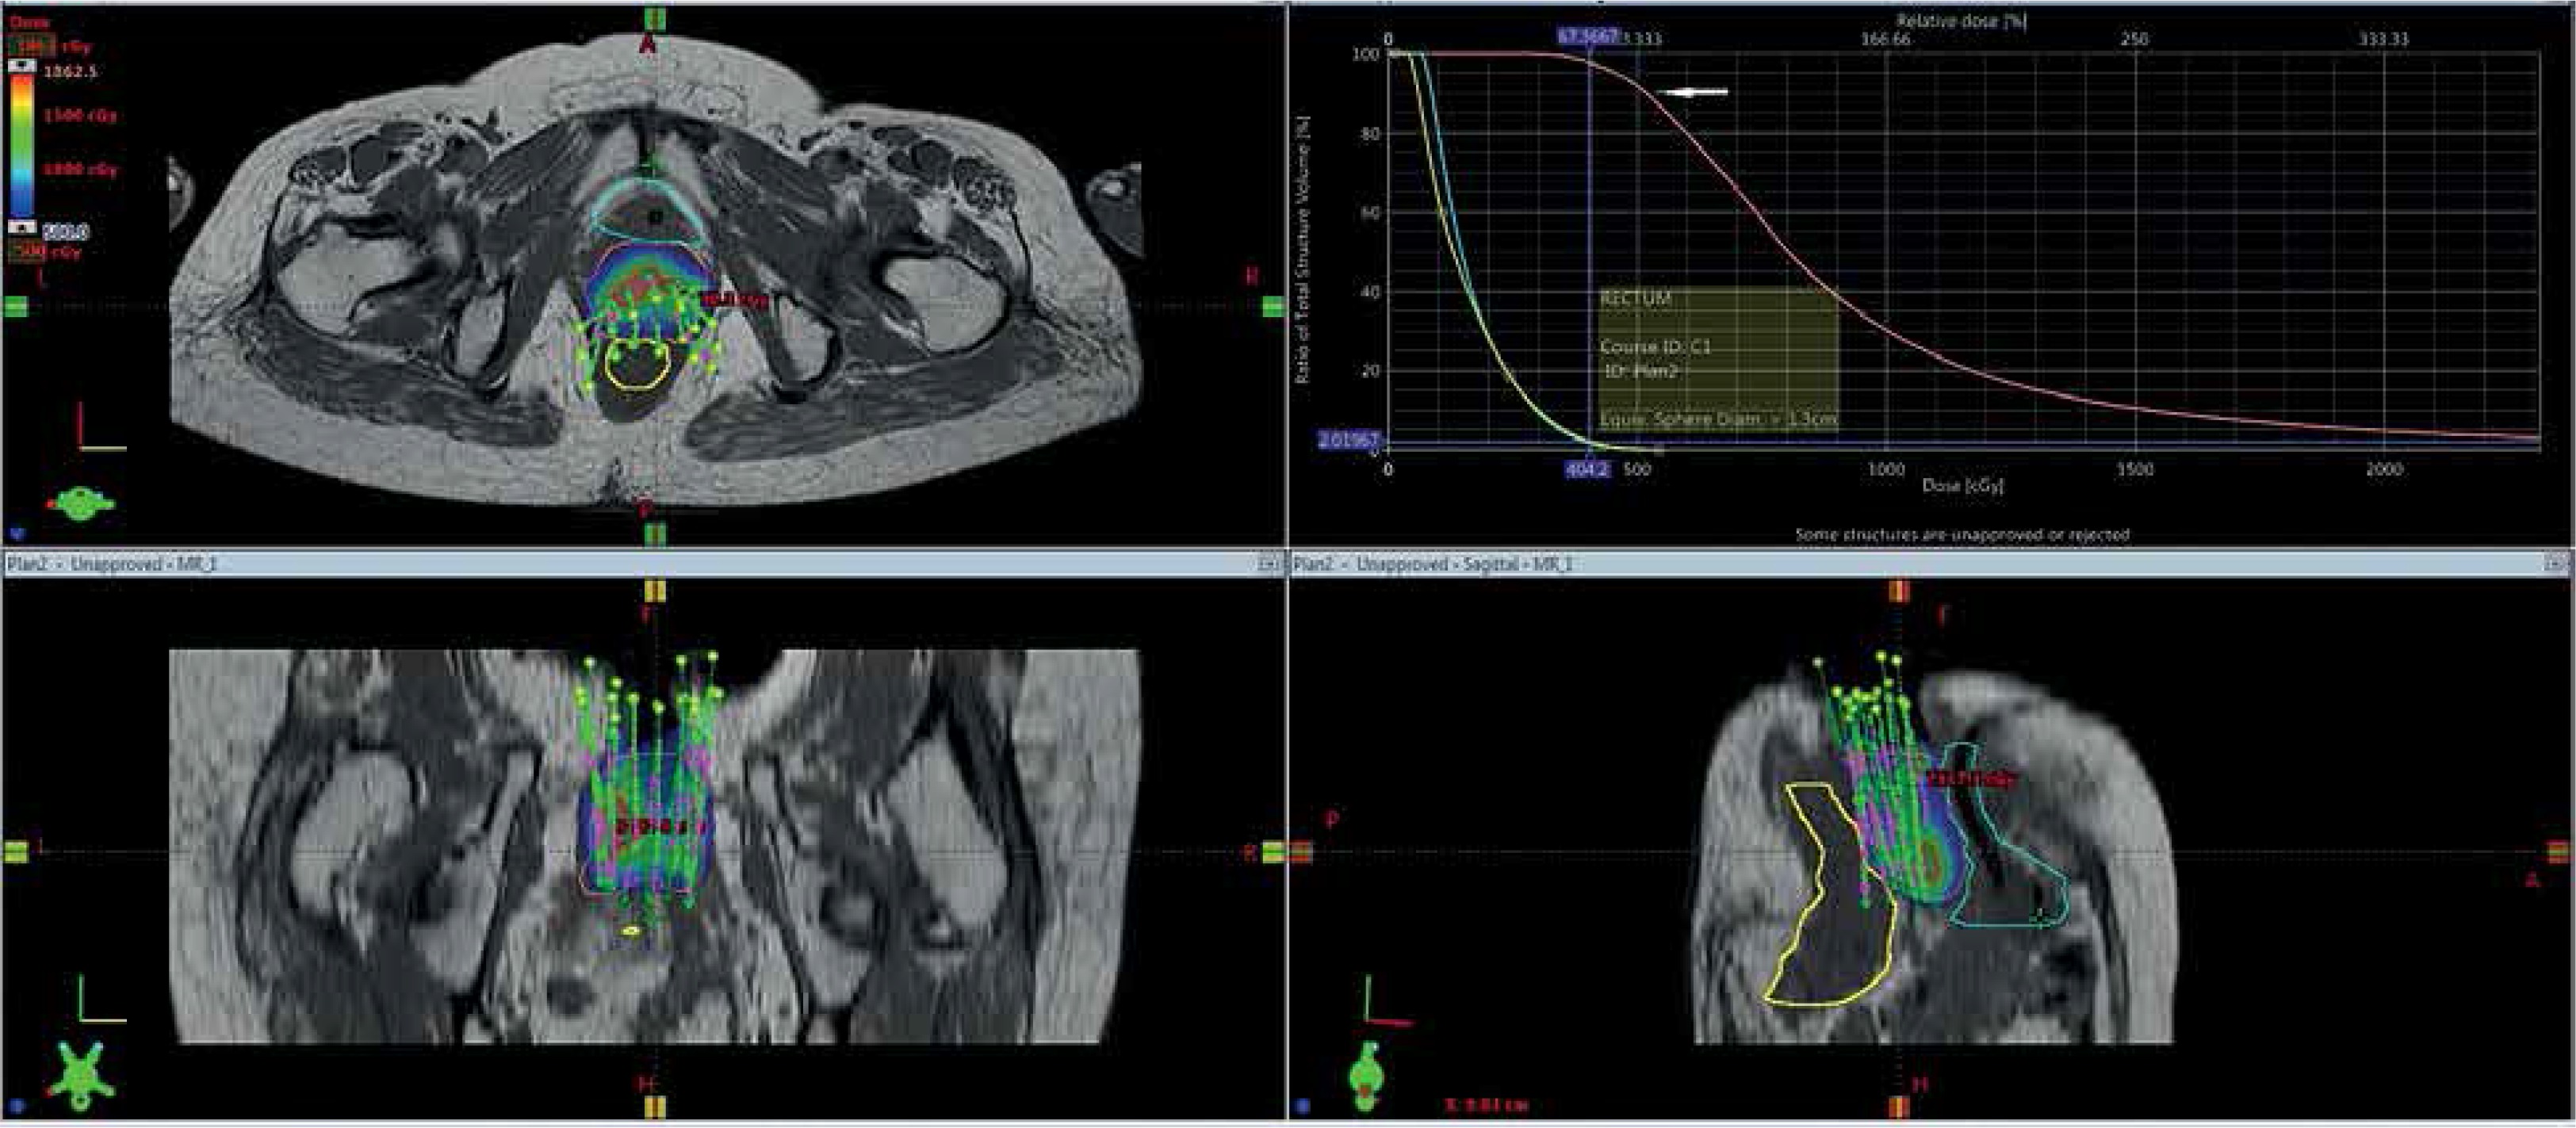

Gross tumor volume, high-risk clinical target volume (HR-CTV), intermediate-risk clinical target volume (IR-CTV), and OARs were delineated with the use of MR T2 weighted images, following GEC-ESTRO guidelines. HR-CTV delineation was challenging, as pre-brachy MR images were not available. This was overcome by changing the contrast resolution and EUA findings (Figure 1). T1 weighted images were helpful for a catheter reconstruction, and the catheters were better appreciated as black straight lines without any interruptions. Haack et al. showed that plastic catheters are well suited for MR-based reconstruction in T1 images and all catheters were visible without artifacts [9]. Depending of the extent of disease, the active lengths of the implant ranged from 6-8 cm. The dose prescribed was 20 Gy in 4 fractions (30 Gy low-dose-rate [LDR] equivalent [EQD2]) to HR-CTV, 6 hours apart, and delivered over two days. Doses of 2 cc of bladder and rectum were restricted to less than 4.0 and 3.7 Gy per fraction, respectively. With our initial experience, the dose escalation was considered to be 6 Gy per fraction. Treatment plans were performed using volumetric optimization with 5 mm dwell position (Figure 2). The OARs constraints were met using manual dragging of isodose lines. The treatment was executed using 192Ir Gammamed Plus HDR remote afterloading machine (Varian Medical Systems, Palo Alto, CA, USA), with 192Ir high activity of 10 Ci max, source of 4.6 mm active length and 0.9 mm in diameter.

The prescribed dose to HR-CTV was 5 Gy × 4 fractions (30 Gy LDR equivalent). The dose to HR-CTV and OARs were analyzed using DVH. Dose values were biologically normalized to equivalent doses of 2 Gy fractions (EQD2, equivalent to 50 cGy/h LDR, using spreadsheet of the Medical University in Vienna) by applying the linear-quadratic model. The 3D dose-volume parameters for five patients are shown in Table 1. The average tumor volume was 67 cc, the average dose to 90% of HR-CTV (D90) volume was 5.7 Gy (79 Gy EQD2), and the average dose to 100% of HR-CTV (D100) volume was 3.8 Gy (68 Gy EQD2). The average doses of 2 cc of rectum and bladder were 3.71 Gy and 4.04 Gy, dose maximum were 70 Gy and 76 Gy EQD2, respectively. High-dose volumes V150 and V200 were 28 cc and 14 cc, respectively, with close proximity to the catheters.